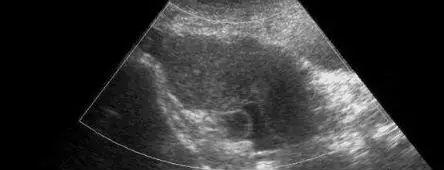

盆腔积液超声影像